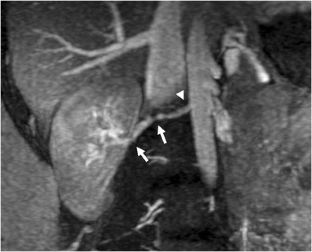

Fig. 1